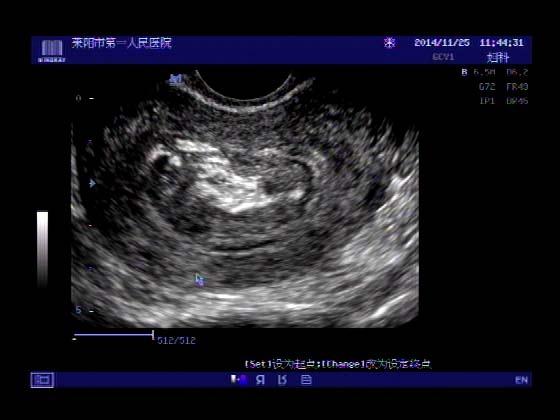

超声入门贴379---------粘膜下肌瘤(阴超的魅力)

女,43岁,月经量多3个多月,加重一个月

外院彩超检查提示:子宫后肌壁略高回声团------肌瘤?息肉?,盆腔少量积液

今天来我院检查:

巧妇难为无米之炊,经腹部超声确实很难定,阴超一目了然,乡镇医院诊断水平的提高更迫切的需要高档仪器的引进!